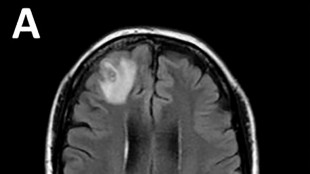

Cirujanos en EEUU realizan el primer trasplante de ojo completo del mundo